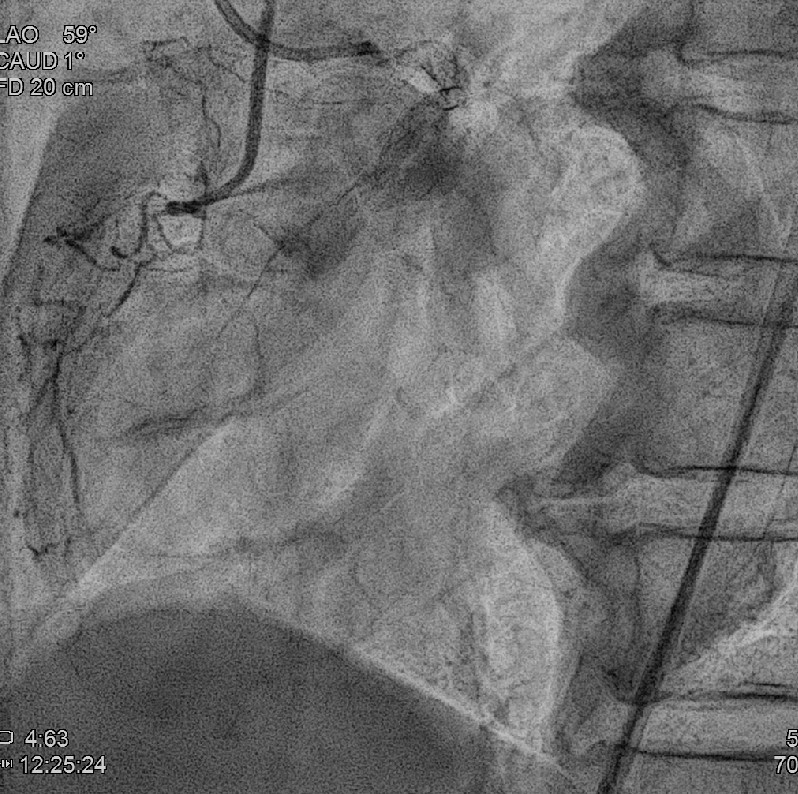

Coronary angiography revealed 81% in-stent restenosis at the right coronary artery ostium, worsened since February 2025. Proximal and mid RCA stents were patent; distal RCA was patent but smaller in caliber . Left main and LAD stents showed no progression, though 30–60% restenosis was seen in proximal to mid LAD. Left circumflex artery was nearly totally occluded from ostium to proximal segment, with preserved flow in mid and distal segments, similar to prior study.

We advanced a 6F JR 4.0 SH 100cm guiding catheter and crossed the RCA ostial lesion using a Fielder FC guidewire. Pre-dilatation was performed with Ryurei 1.5¡¿15mm balloon. IVUS was then performed, revealing a patent stent in the proximal to mid RCA. However, the ostial RCA stent was under-expanded, with smooth muscle compressing the stent from outside. Balloon pre-dilatation was carried out using an NC Euphora 4.0¡¿12mm balloon, inflated up to 22 bar. However, the lesion was resistant and could not be fully dilated. We then applied a 4.0mm intravascular lithotripsy balloon with a total of 100 shocks delivered. But the effect was still minimal. The IVUS showed limited additional plaque fracture or vessel expansion. We tried NC Sapphire II 4.5¡¿8 mm balloon inflation to 18 bar, but it was ineffective due to balloon slippage. The angiogram after oversized NC dilation showed residual stenosis of 59%. We then selected a Wolverine Cutting Balloon 4.0¡¿10 mm and initiated dilation to 6 bar, which resulted in easy slippage again. Subsequent oversized dilations were performed at 18 bar, after which the lesion was successfully dilated. Using a Runthrough Floppy guidewire with the floating wire technique, a drug-eluting stent Biofreedom Ultra 4.0¡¿14 mm was deployed in the ostial RCA ISR. We inflated at 14 bar for 14 seconds, repeated twice. Final post-dilatation was performed with an Accuforce 4.0¡¿15mm balloon. The final IVUS showed good stent placement and expansion. We closed the procedure.